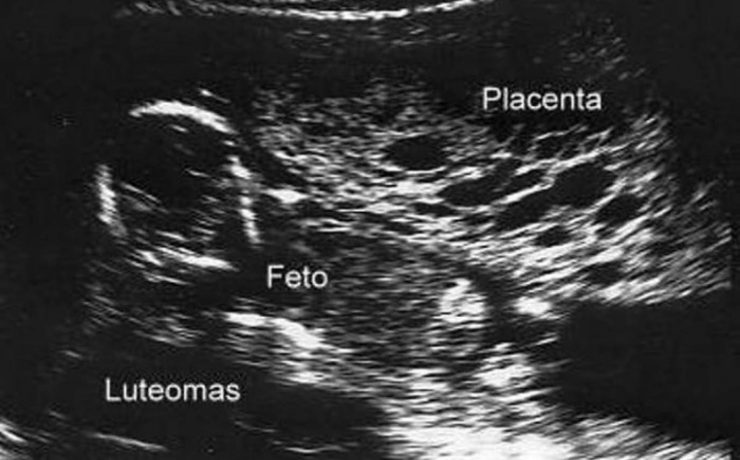

La apendicitis aguda durante el embarazo constituye la causa más frecuente de abdomen agudo quirúrgico no obstétrico, reportándose a nivel mundial una incidencia de 0.1 a 1.4 casos por cada 1,000 embarazadas. Algunos estudios en América Latina han reportado una incidencia aproximada de 1 por cada 1,200 embarazos. El diagnóstico